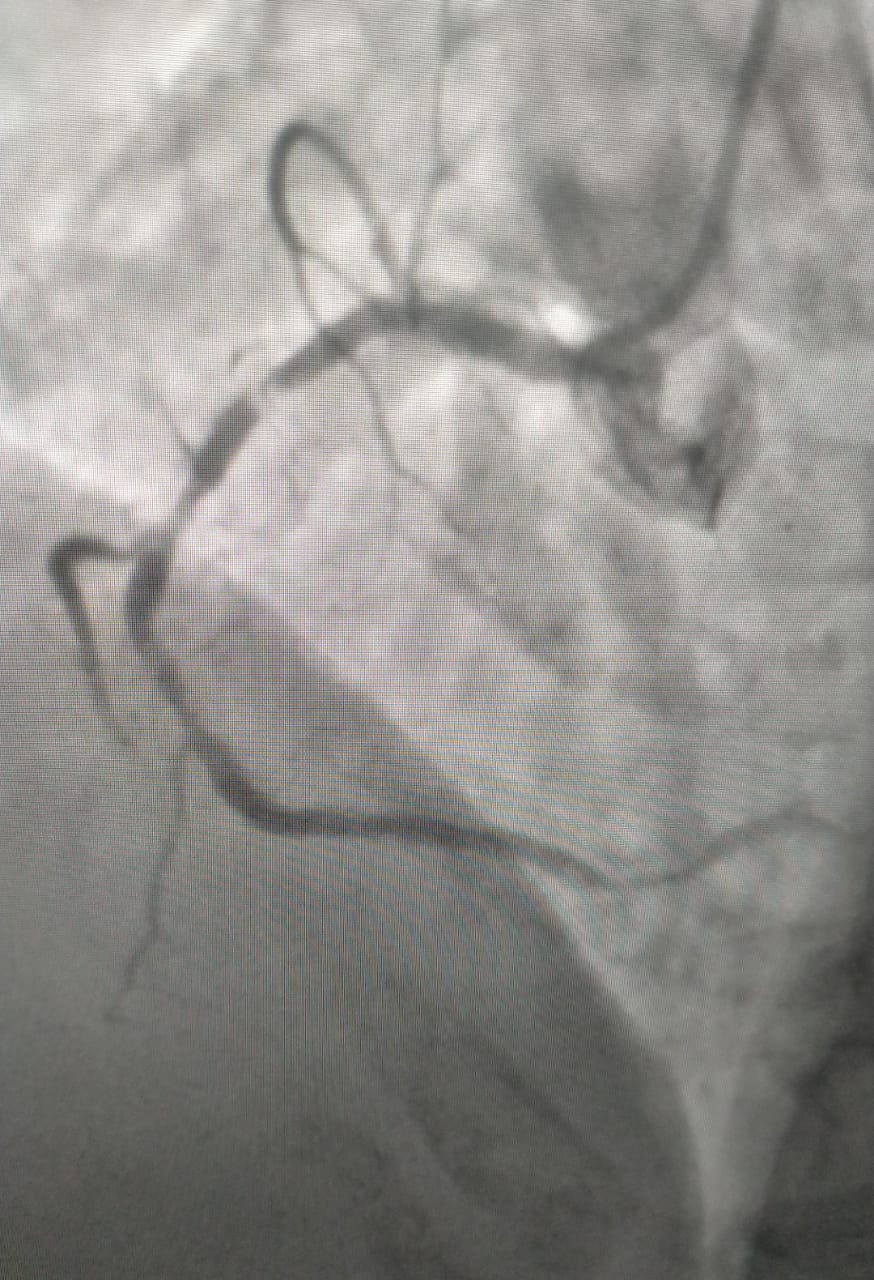

Successfully performed the first RiForm PRO case in Central India by Dr. Sarita Rao at Apollo Hospital for a balloon-uncrossable, heavily calcified lesion. With no gas requirement, dual cutting action, and combined orbital & rotational technology, it enables precise and effective plaque modification. A single-operator friendly, Made in India 🇮🇳 innovation for complex coronary interventions.